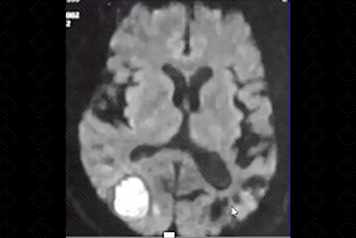

Texto alternativo para a imagem Figura 2. Créditos: Dra. Elazir Mota - Rio de Janeiro/RJ

Descrição da figura 2: Imagem hiperdensa, compatível com sangramento no tálamo direito (seta amarela).

• Hemorragia hipertensiva: Hematoma focal agudo ou micro-hemorragias. Localizações mais comuns: putâmen e cápsula externa (mais comuns, cerca de 60-65% dos casos). Outras localizações típicas são tálamo, centro semioval, cerebelo e ponte (f iguras 1 e 2);